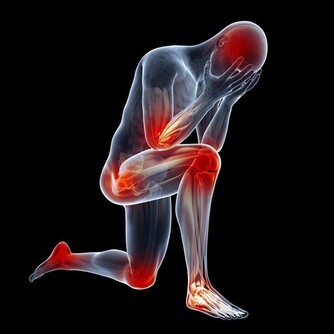

三、肢體麻木

許多血栓患者在開始時表現出不同程度的麻木感。你可能會以為是壓到了或者是累著了,直到發展為疼痛才會想到就醫。但其實這可能是由於心臟或者其他部位的血栓進入了你的動脈。

腿動脈栓塞以後,這部分腿部就會缺血,變得皮膚蒼白、溫度降低,甚至連足背動脈都可能摸不到了。